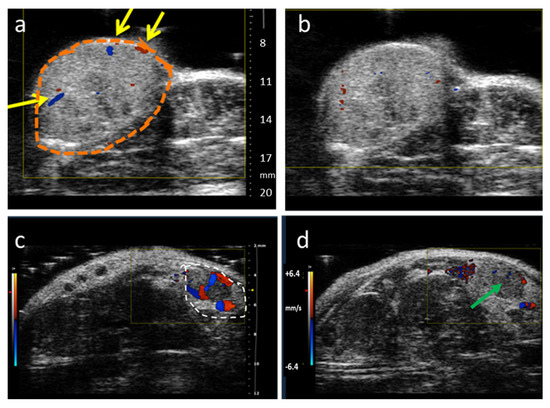

- Abma, E.; Stock, E.; De Spiegelaere, W.; Van Brantegem, L.; Vanderperren, K.; Ni, Y.; Vynck, M.; Daminet, S.; De Clercq, K.; de Rooster, H. Power Doppler ultrasound and contrast-enhanced ultrasound demonstrate non-invasive tumour vascular response to anti-vascular therapy in canine cancer patients. Sci. Rep. 2019, 9, 9262. [Google Scholar] [CrossRef] [PubMed]

- Zhang, P.; Chen, Y.; Liu, J.; Yang, Y.; Lv, Q.; Wang, J.; Zhang, L.; Xie, M. Quantitative Evaluation of Combretastatin A4 Phosphate Early Efficacy in a Tumor Model with Dynamic Contrast-Enhanced Ultrasound. Ultrasound Med. Biol. 2018, 44, 840–852. [Google Scholar] [CrossRef]